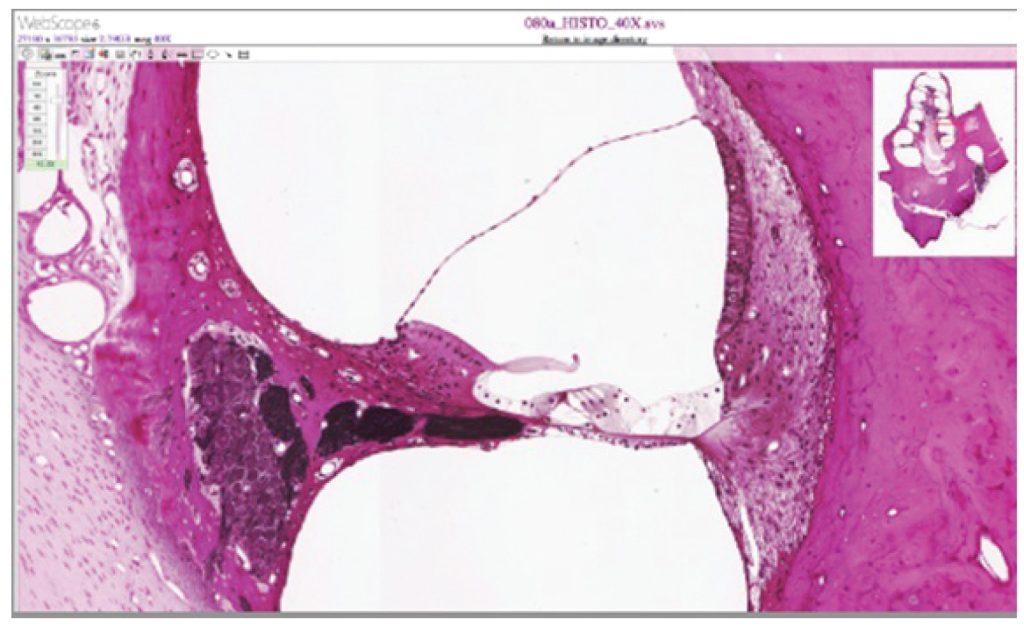

This micrograph shows the ultrastructure of the cochlea.

Figure 9.7 Cochlea and Organ of Corti LM × 412. (Micrograph provided by the Regents of University of Michigan Medical School © 2012)